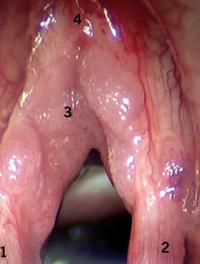

Les dermohypodermites bactériennes nécrosantes-fasciites nécrosantes (DHBN-FN) sont des infections cutanées rapidement progressives rares et graves avec une morbi-mortalité élevée. La principale difficulté réside dans le fait d’établir un diagnostic rapide pour permettre une prise en charge chirurgicale précoce qui conditionne le pronostic fonctionnel et vital du patient. Il faut distinguer, d’une part, les dermohypodermites bactériennes non nécrosantes (DHB) assimilées [...]